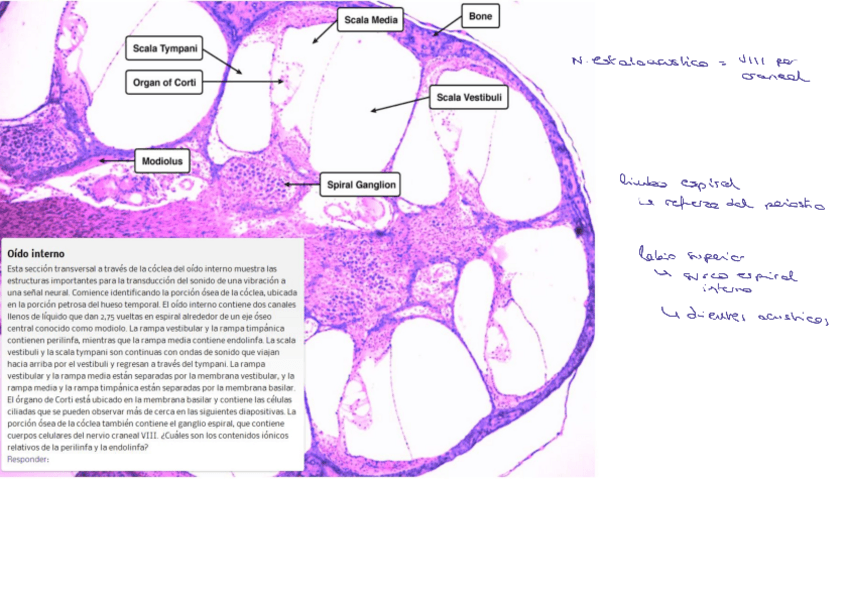

oido-ppt.pdf

He publicado nuevos apuntes de 1º Histología Médica: OIDO.pdf

6 páginas